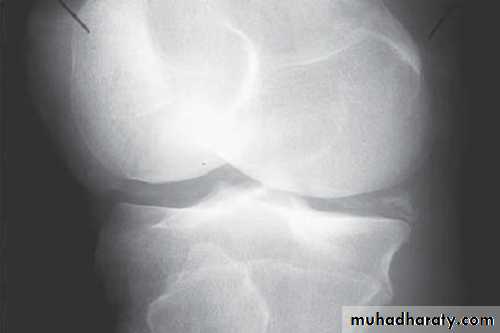

Radiographs

Radiograph of the joint: Although frequently normal, a radiograph may disclose important information.It may help in diagnosing an unsuspected fracture, osteonecrosis, osteoarthritis, or a juxtaarticular bone tumor.

The presence of chondrocalcinosis, a radiologic feature of CPPD disease, increases suspicion for a pseudogout attack.

Tumor, chronic fungal or mycobacterial infection, and other indolent destructive processes may be revealed.